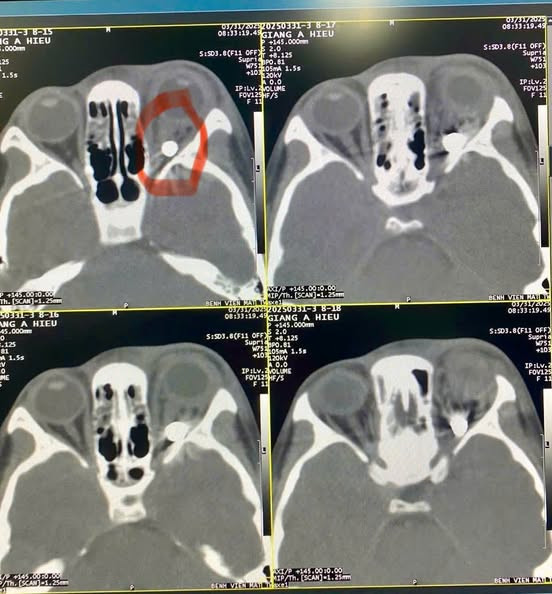

Bệnh viện Mắt Trung ương vừa tiếp nhận một trường hợp bệnh nhi 9 tuổi tên là Giàng A Hiếu (dân tộc H’Mông, xã Chiềng Cang, huyện Sông Mã, tỉnh Sơn La) trong tình trạng mắt trái bị rách góc mi trong, thị lực sáng tối âm tính, đặc biệt qua kết quả chụp chiếu phát hiện có dị vật hình tròn trong hốc mắt kích thước khoảng 3-4mm, nghi là viên bi sắt.

| Kết quả chụp chiếu phát hiện có dị vật hình tròn trong hốc mắt kích thước khoảng 3-4mm, nghi là viên bi sắt - Ảnh BVCC |